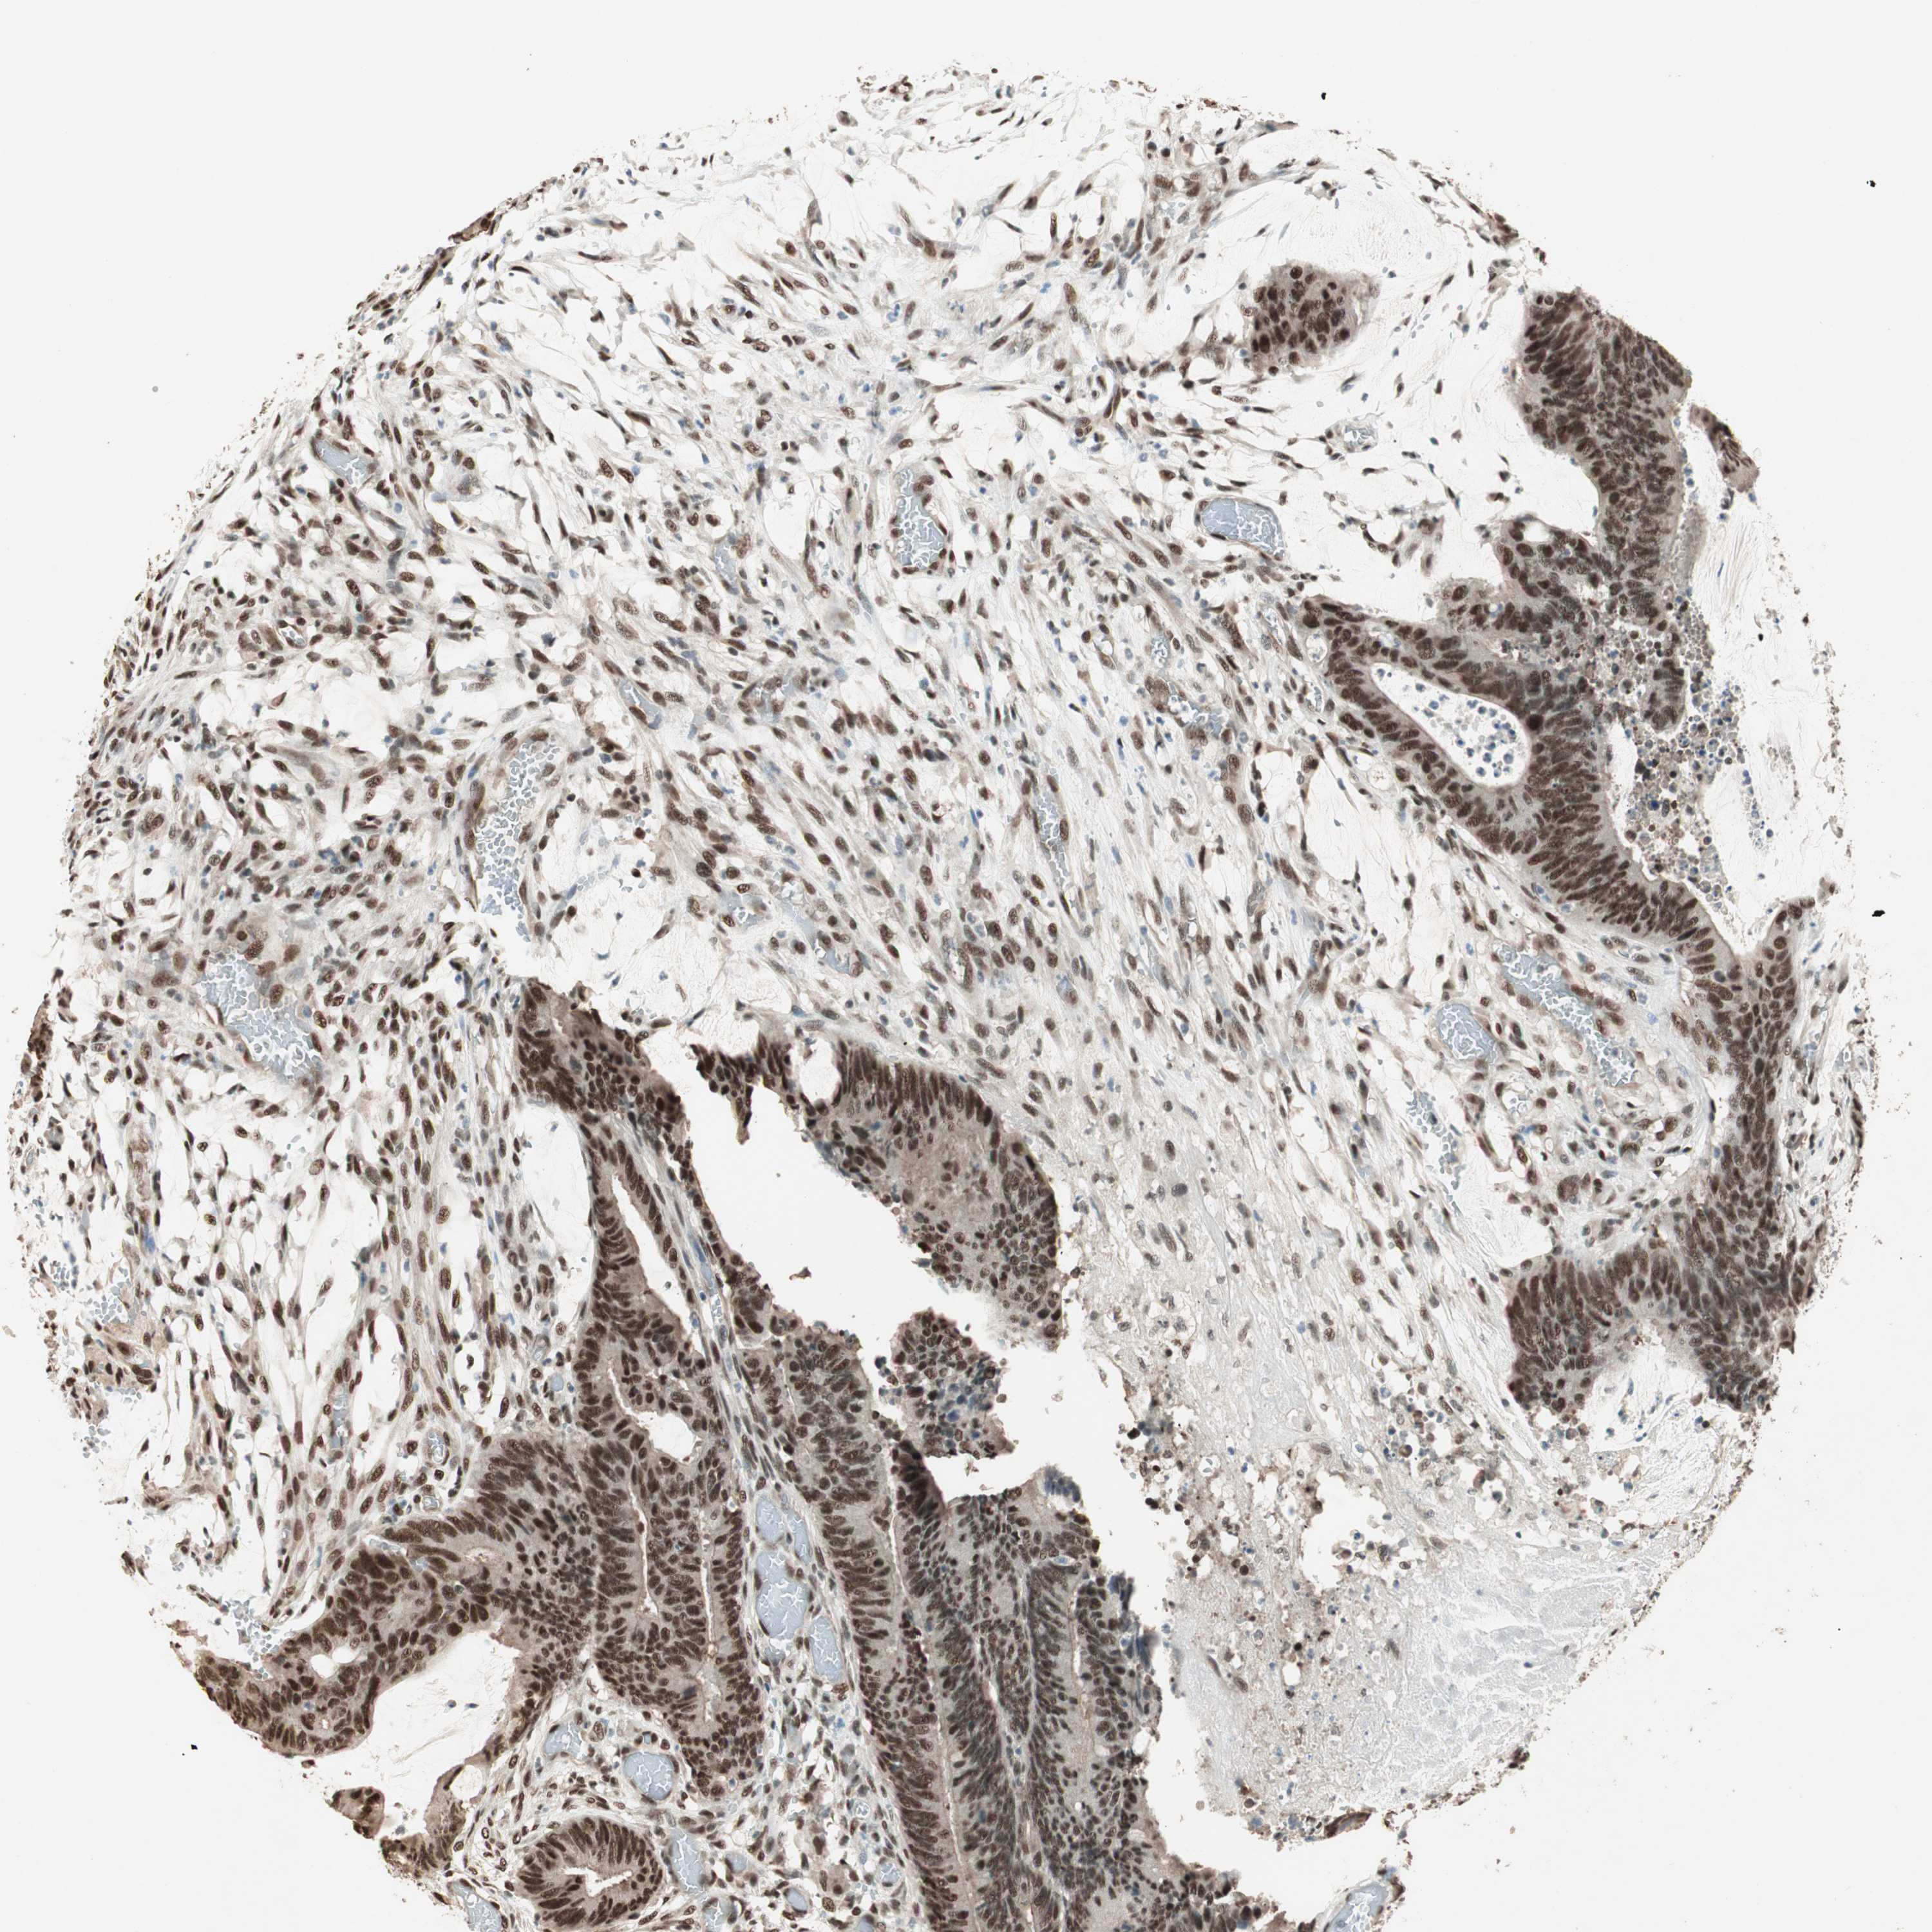

CANCER COLORECTAL CANCER Show tissue menu

Colorectal cancer

Colon adenocarcinoma